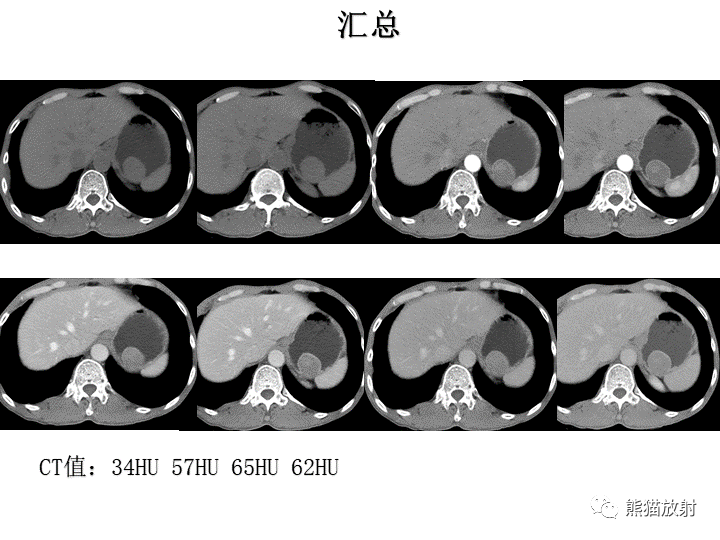

【病例】胃间质瘤VS神经鞘瘤-4